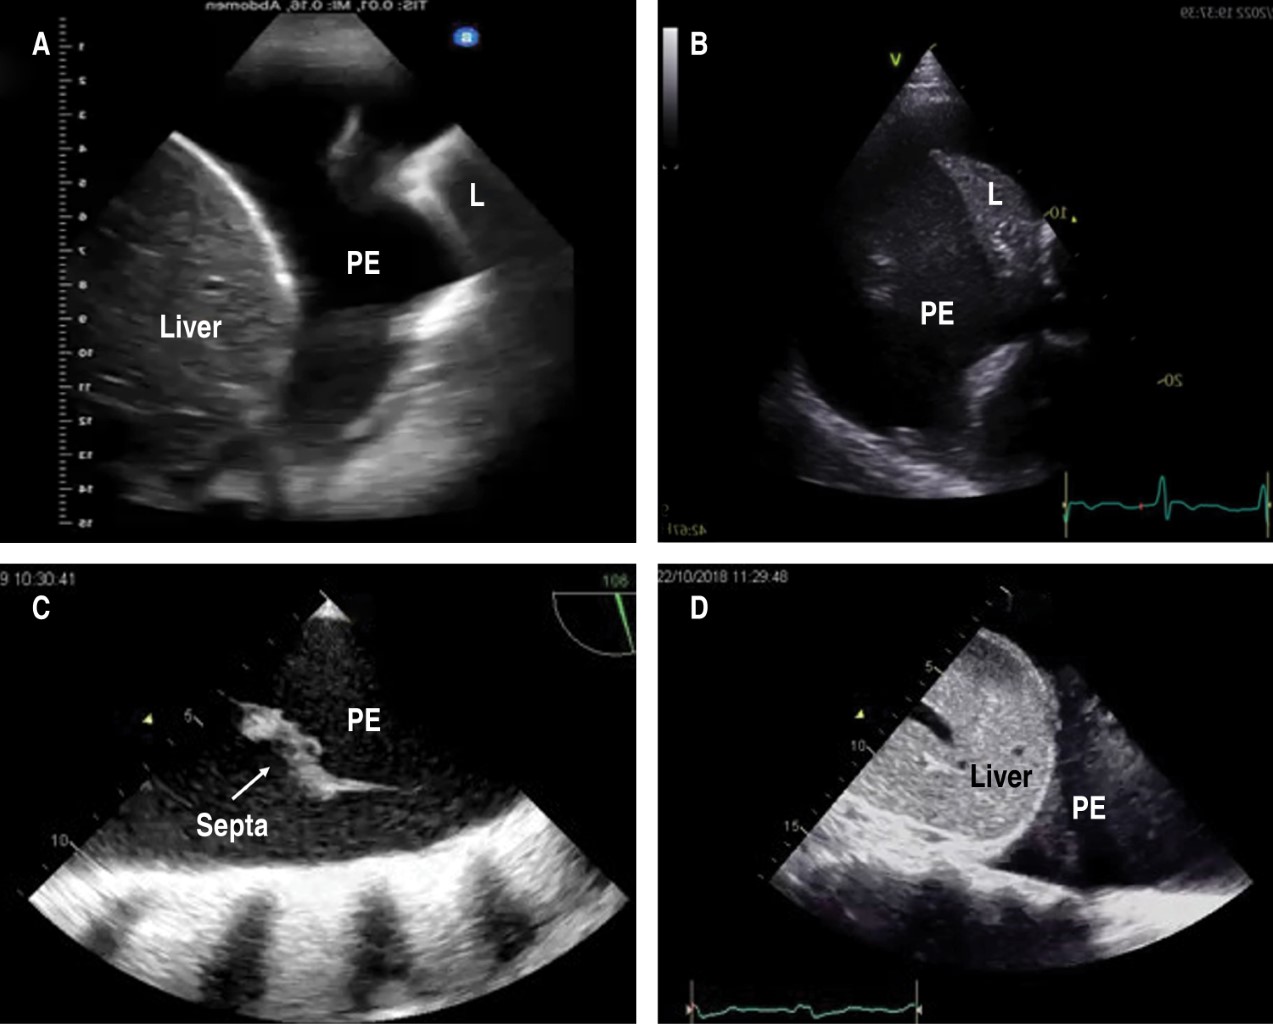

Utilidad de la fórmula de Balik para la cuantificación del derrame pleural por ultrasonido en el posoperatorio de cirugía cardiaca

Cruz-Rodríguez, Camelia1; García-Cruz, Edgar1; Gopar-Nieto, Rodrigo1; Lazcano-Díaz, Emmanuel1; Ordaz-Figueroa, Diana Lizbeth1; Elizalde-Silva, José Luis1; Rojas-Velasco, Gustavo1; Manzur-Sandoval, Daniel1